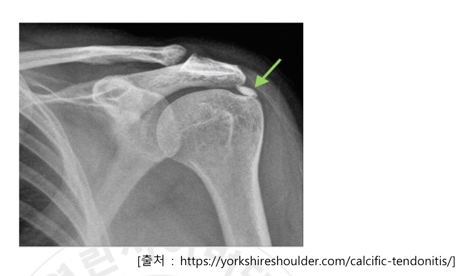

3. 석회화건염 (Calcifictendnitis)

마지막은 석회화건염입니다.이름만 들어도 어떤 증상인지 알 수 있을까요?석회화건염이라는 힘줄(근) 조직에 석회가 침착되고 이로 인해 통증이 생기는 질환으로 어깨관절 주변 힘줄에서 가장 많이 발생하는데, 석회가 힘줄에 침착되어 통증을 유발하는지는 명확하지 않다고 합니다.

주변 조직의 저산소 상태, 국소 압박, 어깨 관절의 과사용 또는 연령에 따른 변화나 퇴행성 변화 등이 가장 깊은 관련이 있습니다.

석회화건염 증상으로는 밤에 잠들지 못할 정도로 어깨 통증이 심하고 팔이 툭툭 찌르는 듯한 날카로운 통증이 느껴지며 간혹 통증이 나타났다 사라지는 일이 반복되며 팔을 앞이나 옆으로 들어올리기 어렵다는 점 등이 있습니다.